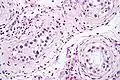

Intratubular germ cell neoplasia. H&E stain.

GCNIS is not palpable, and not visible on macroscopic examination of testicular tissue. Microscopic examination of affected testicular tissue most commonly shows germ cells with enlarged hyperchromatic nuclei with prominent nucleoli and clear cytoplasm. These cells are typically arranged along the basement membrane of the tubule, and mitotic figures are frequently seen. The sertoli cells are pushed toward the lumen by the neoplastic germ cells, and spermatogenesis is almost always absent in the affected tubules. Pagetoid spread of GCNIS into the rete testis is common. Immunostaining with placental alkaline phosphatase (PLAP) highlights GCNIS cell membranes in 95 percent of cases. OCT3/4 is a sensitive and specific nuclear stain of GCNIS.[3]